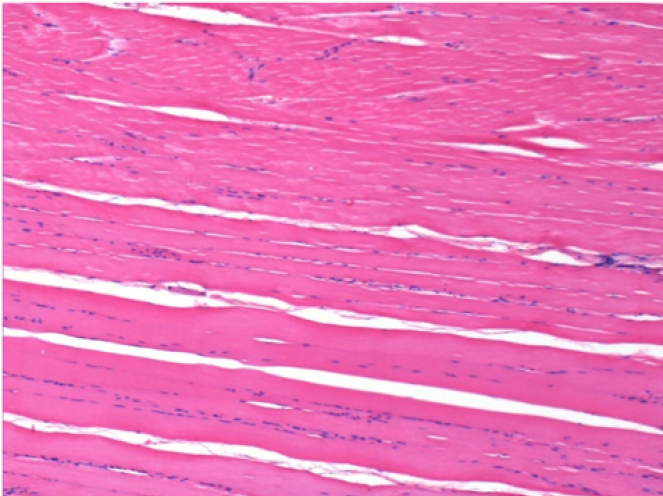

1 month after Endopeel Injection

1 month after Endopeel Injection 0.1ml in the right pretibial muscle.

What is seen in black on the pictures is not a necrosis like could imagine some scientifics !

In fact, 4 conclusions have to be taken in consideration

- an artefact of coloration

- an absence of necrosis

- an apoptosis

- a bioregenerative process

L : Control-100xD30

R:100xD30

R :400xD30